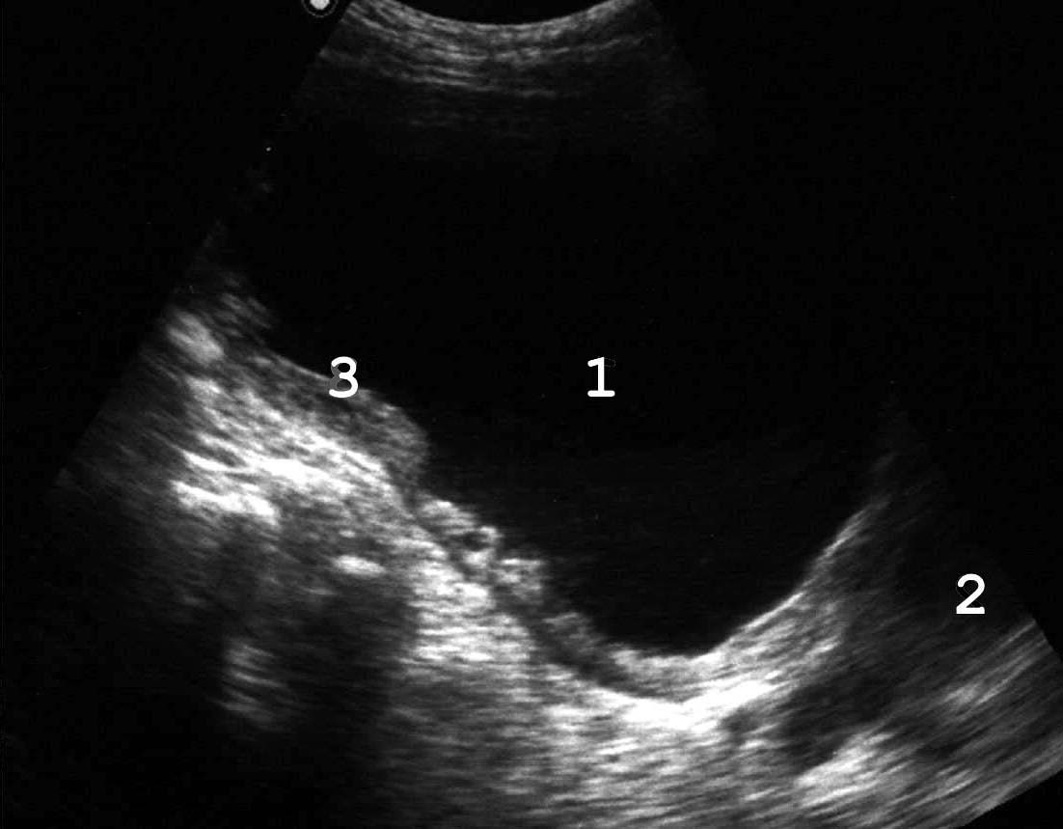

Мочевой пузырь представляет собой полый орган, расположенный в малом тазу, за лонным сочленением. Емкость пузыря от 200 до 600 мл, в патологических условиях может достигать 1000−2000 мл. У здорового человека первый позыв на мочеиспускание возникает при объеме мочевого пузыря 100−150 мл, выраженный позыв − при заполнении 250−350 мл. Анатомически в мочевом пузыре различают верхушку, шейку, дно и тело. Верхушка − место перехода пузыря в среднюю пузырно-пупочную связку, различима только при его наполнении (1 − см. рис. 1). Дно (4) − наиболее широкая нижнезадняя часть мочевого пузыря, обращенная у мужчин в сторону прямой кишки, у женщин в сторону матки и верхней части передней стенки влагалища. Шейка − суженная часть мочевого пузыря, граничит с мочеиспускательным каналом. Средний отдел, расположенный между верхушкой и дном мочевого пузыря, называется телом. мочевой пузырь имеет переднюю, заднюю и две боковые стенки (2, 3), переходящие одна в другую без четких границ. Мочепузырный треугольник Льето (5) образован устьями мочеточников и внутренним отверстием мочеиспускательного канала, основанием его является межмочеточниковая складка. Начальный отдел мочеиспускательного канала охватывается предстательной железой (6).

Рис. 1. Сонограмма мочевого пузыря мужчины в норме. Остаточный объем мочи с достаточной для практики точ¬но-стью можно определить по формуле a х b x c x 0,57 [50]. (Поперечное [A] и продольное [Б] сканирование, конвексный датчик 5 МГц, “Logiq-500”).